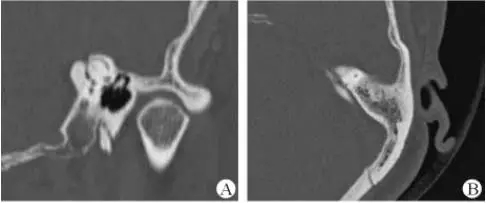

1、上半規(guī)管裂綜合征

內(nèi)耳結(jié)構(gòu)非常微妙。即使是內(nèi)耳中大頭針樣的孔洞也能造成平衡失調(diào)。患者常常不敢進(jìn)行如走路或轉(zhuǎn)頭的日常活動。此罕見疾病,醫(yī)學(xué)專家預(yù)估至少影響著人口的1%。可造成惡心,眩暈以及對噪聲極高的敏感性。病人還常常抱怨他們能聽到血管跳動的聲音。其中一位患者曾告訴耳科專家,他都能聽到自己轉(zhuǎn)動眼睛的聲音。

診斷及治療

醫(yī)生若懷疑此病將會安排內(nèi)耳CT掃描。在大多數(shù)案例中,一旦此病被耳鼻喉科醫(yī)生或其它聽力健康專家確診,則可實行手術(shù)治療。外科手術(shù)風(fēng)險包含聽力損失以及神經(jīng)損傷;重建及復(fù)原需內(nèi)耳的治療以及大腦的重塑。